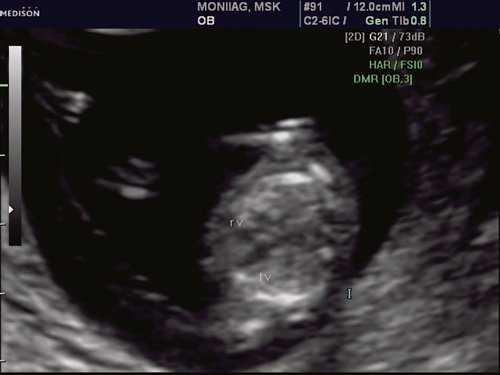

Исходя из особенностей внутрисердечной гемодинамики плода, для диагностики коарктации аорты были предложены косвенные признаки патологии в антенатальном периоде: дилатация правого желудочка и его гипертрофия (см. рис. 3), дилатация легочной артерии [6, 7, 14]. Авторы считают, что это достоверные признаки и встречаются они достаточно часто (в 18 из 24 случаев верифицированных диагнозов коарктации аорты). Поэтому была предложена оценка индексов отношения полости правого желудочка к левому (в норме - 1,1) и легочной артерии к аорте (у здоровых - 1,2). Исходя из увеличения этих параметров, можно предположить наличие затрудненного выброса в аорту или гипоплазию дуги аорты. Тем не менее, по данным предложивших эти косвенные признаки авторов, такие изменения выявляются только в 30% наблюдений (рис. 4).

Рис. 4. Диспропорция размеров желудочков сердца при коарктации аорты. RV - правый желудочек; LV - левый желудочек; AO DESC - поперечное сечение нисходящего отдела аорты.

При эхокардиографии изучались четырехкамерный срез сердца плода (рис. 1) и срез через три сосуда (рис. 2). УЗИ проводилось трансабдоминальным датчиком, лишь при необходимости (затрудненная визуализация) использовался внутриполостной датчик. Четырехкамерный срез сердца плода при ультразвуковом сканировании трансабдоминальным датчиком визуализировался в 85% случаев, срез через сосуды - в 73%, при использовании трансвагинального датчика эти цифры существенно возрастали до 100 и 91% соответственно. Оптимизация пренатальной диагностики ВПС может быть достигнута путем строгого соблюдения основных методических правил. При оценке четырехкамерного среза плода необходимо оценить нормальное расположение сердца плода, исключив его эктопию (рис. 3), положение оси сердца плода, что не представляет никаких трудностей, нормальные пропорции и размеры камер сердца, движение створок атриовентрикулярных клапанов должно быть свободным, септальная створка трикуспидального клапана должна располагаться ближе к верхушке сердца (рис. 4). При оценке среза через три сосуда необходимо оценить взаиморасположение сосудов и их диаметр.

Рис. 1. Беременность 12 недель. Четырехкамерный срез сердца плода. Отчетливо видны камеры сердца.